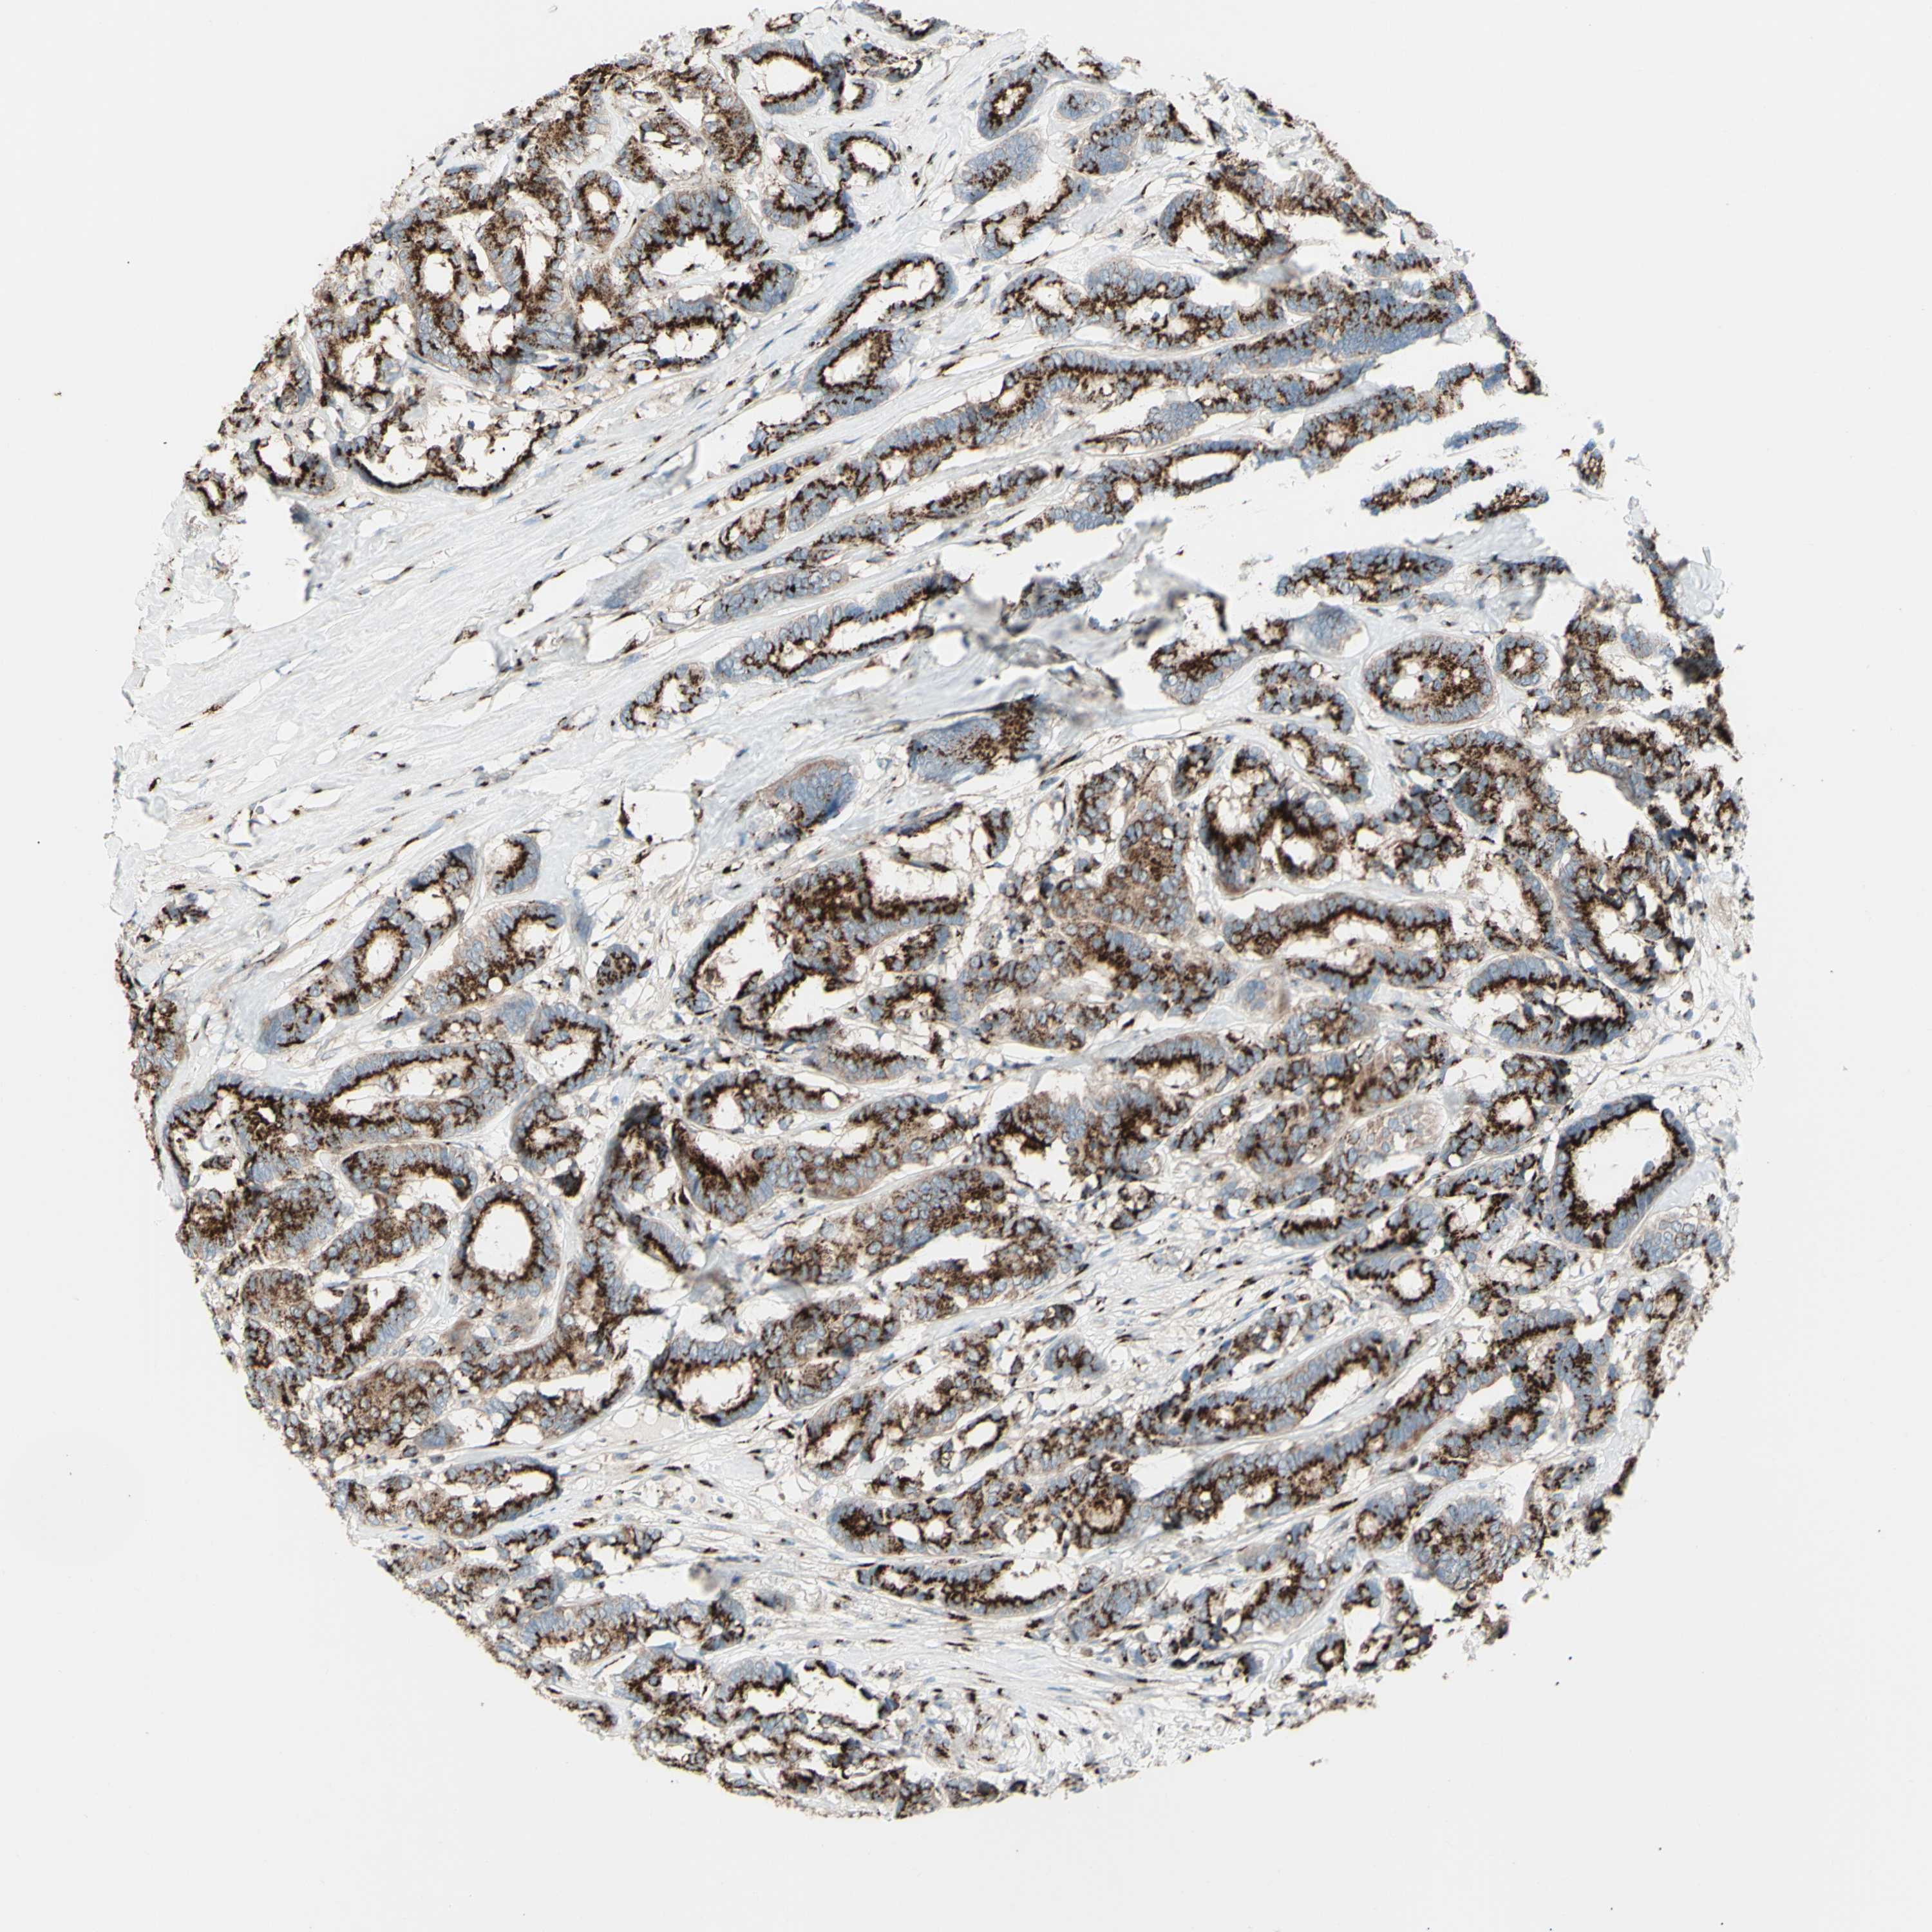

BRCA TCGA BRCA VALIDATION PROTEIN EXPRESSION

ANTIBODIES

AND

VALIDATION